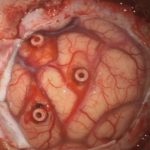

術中写真